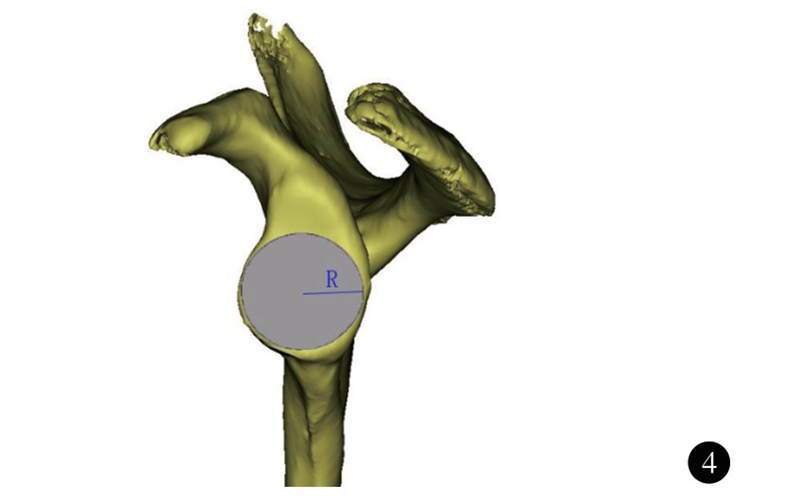

肩胛盂近似梨形,下半部分较上半部分大。在反式肩关节置换术中,肩胛盂侧假体安装在肩胛盂下部,因而肩胛盂下半部分的大小决定了假体的大小。韩国Ji等测量了本国肩胛盂下部的解剖学参数,其中肩胛盂下部半径男女分别为(17.1±2.1)mm和(15.4±1.6)mm,性别之间差异有统计学意义(图4)。

图4 肩胛盂下半部分半径(R)示意图